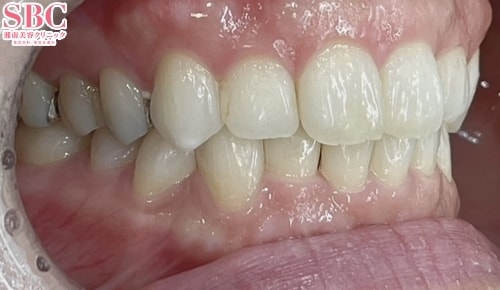

No.357639【美容歯科】上下のガタツキをマウスピース矯正で改善★

施術後12ヶ月後

段差も重なりも改善されました★

段差・重なり解消して綺麗に並びました★

上下の段差が気になるとのことで、インビザラインGoで矯正治療をした症例になります。

歯の重なりや段差、ねじれがあると磨き残しが起こりやすくなりその結果虫歯や歯周病になりやすくなってしまいます。

並びを改善することで今後の歯の健康を維持することに繋がります★